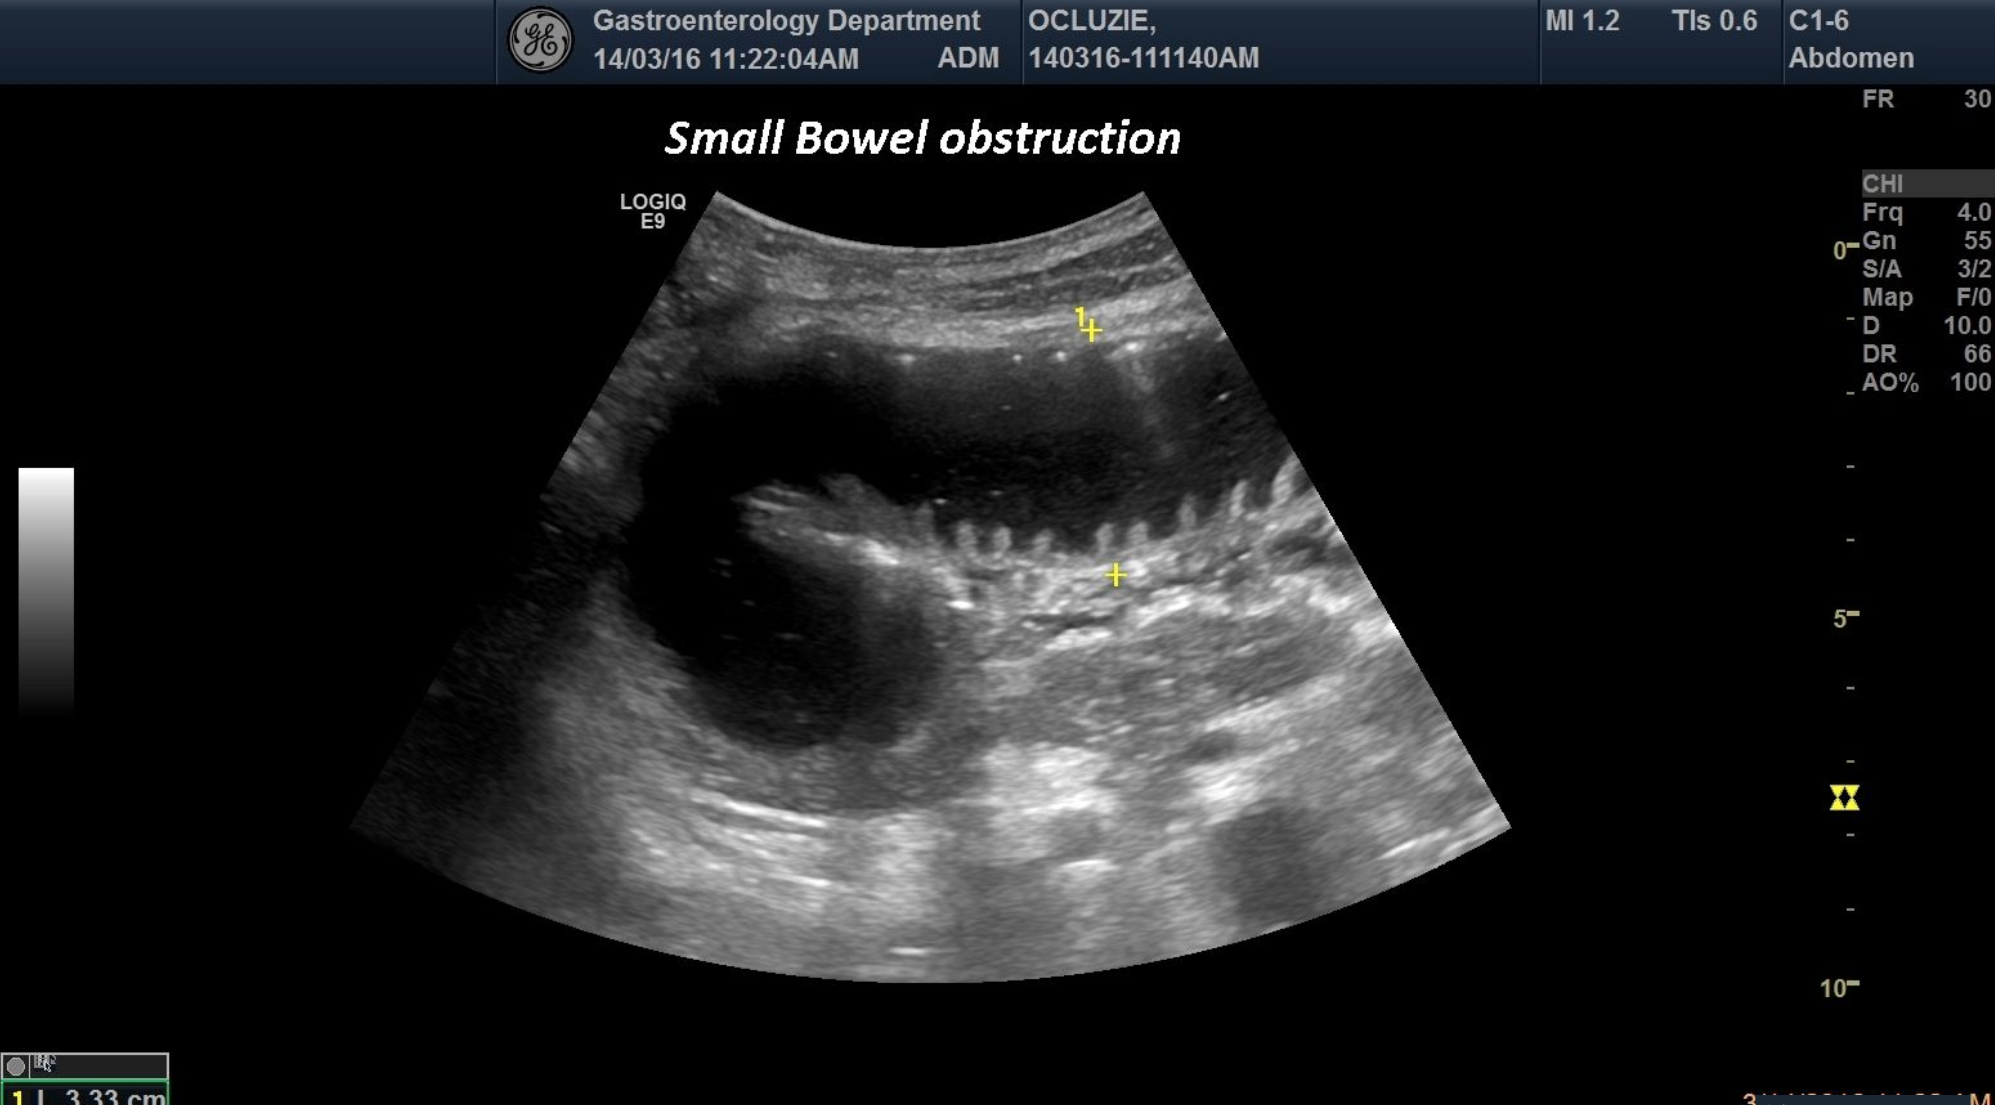

TITLE: Small Bowel obstruction

An 73 years old patient was referred to our department for abdominal pain and severe vomiting.At ultrasound evaluation, we depicted distended small bowel lumen with anechoic content and lack of peristalsis.

small bowel distended,obstruction, lack of peristalsis